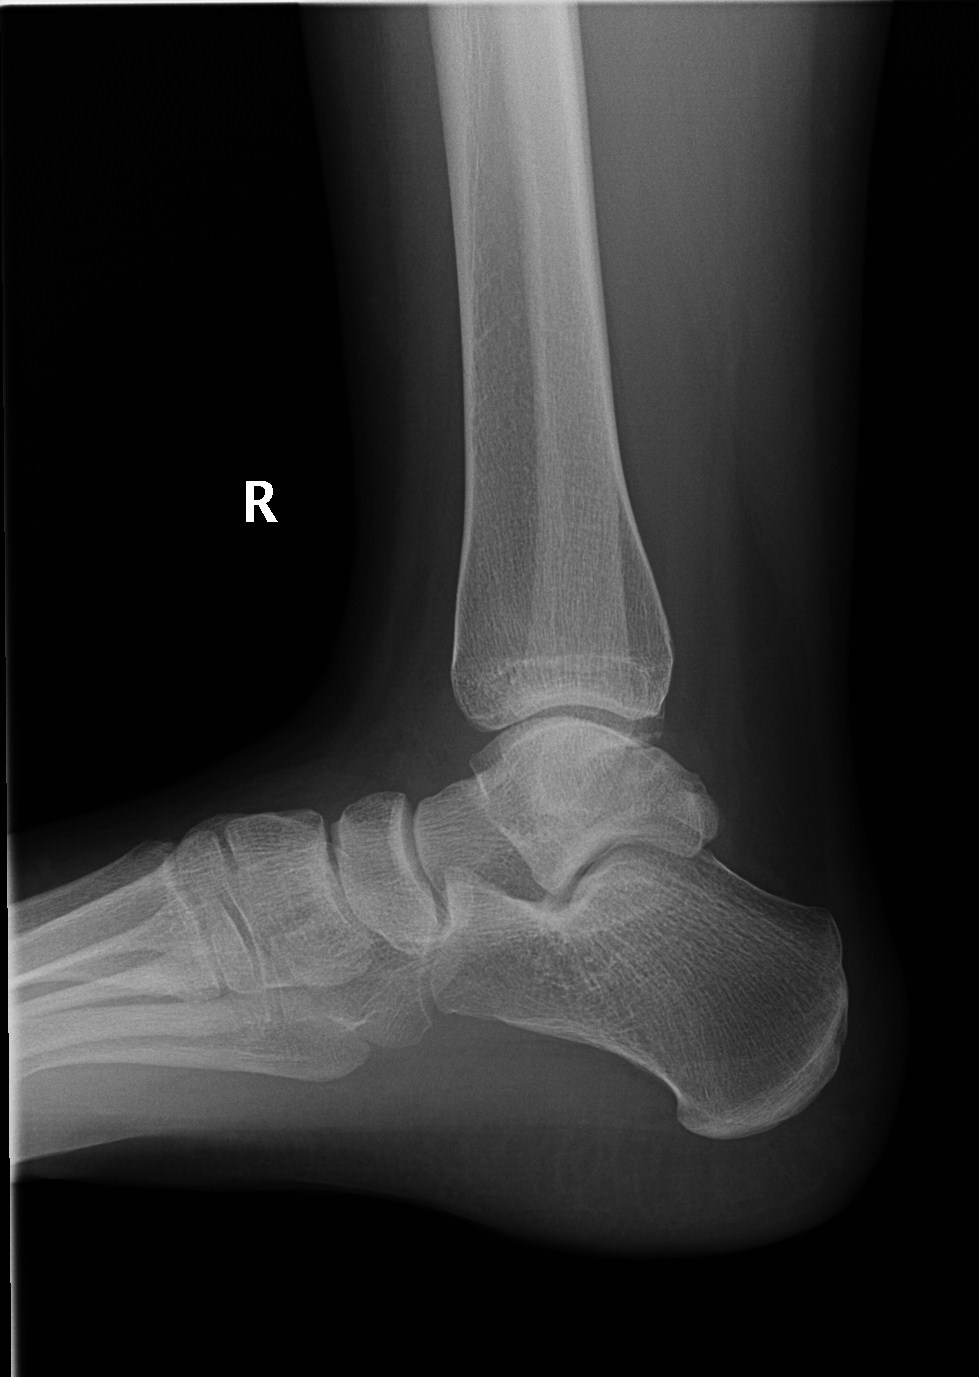

X-rays use invisible

electromagnetic energy beams to produce images

of internal tissues, bones, and organs on film

or digital media. Standard X-rays are performed

for many reasons, including diagnosing tumours or

bone injuries.

When the body undergoes X-rays, different parts

of the body allow varying amounts of the X-ray

beams to pass through. The soft tissues in the

body (such as blood, skin, fat, and muscle)

allow most of the X-ray to pass through and

appear dark gray on the film or digital media. A

bone or a tumour, which is more dense than the

soft tissues, allows few of the X-rays to pass

through and appears white on the X-ray. At a

break in a bone, the X-ray beam passes through

the broken area and appears as a dark line in

the white bone.